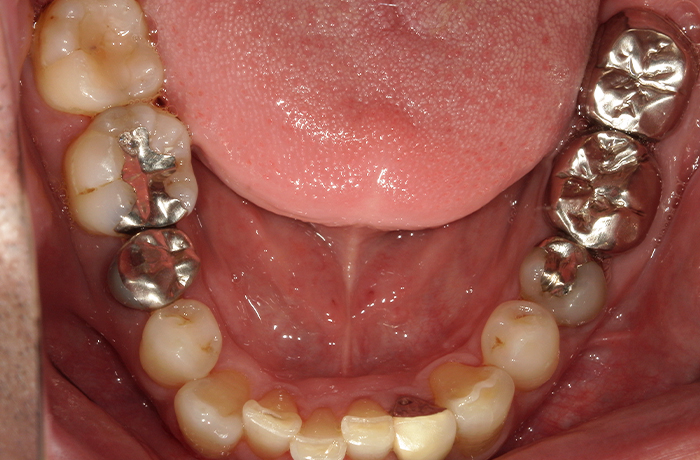

治療後

治療終了後の完成した口腔内と

レントゲン写真

サイナスリフト部の骨再生は良好で、インプラントの安定性も高く、骨吸収や透過像はありませんでした。

最終補綴装着後は咬合バランスが改善し、良好な咀嚼機能が回復。審美性にも優れ、患者様にもご満足いただけました。